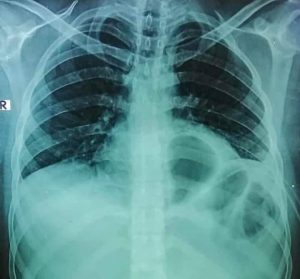

قال الدكتور محمد الجزار استاذ جراحة القلب والصدر بمستشفى بنها الجامعى أن المريض حضر للمستشفي يعاني من نزيف وتجمع دموي بالغشاء البللوري المحيط بالرئة اليسرى نتيجة طعنة وتم تركيب درنقة صدرية لتفريغ الدم المتجمع

أضاف أنه بعد عمل الأشعة المبدئية تبين وجود اشتباه وجود جزء من المعدة والامعاء بالقفص الصدري وبعد تفريغ الدم المتجمع تم تحضير المريض لجراحة استكشاف صدري عاجلة و تبين أن المطواة أدت الي فتحة دخول من القفص الصدري تحت الرئة اليسري مخترقةً الحجاب الحاجز من الأمام ثم اخترقت تجويف البطن وادت الي فتحة خروج في الحجاب الحاجز من الخلف بجانب الشريان الاورطي ب ٢ سم فقط في تجويف الصدر من جديد.